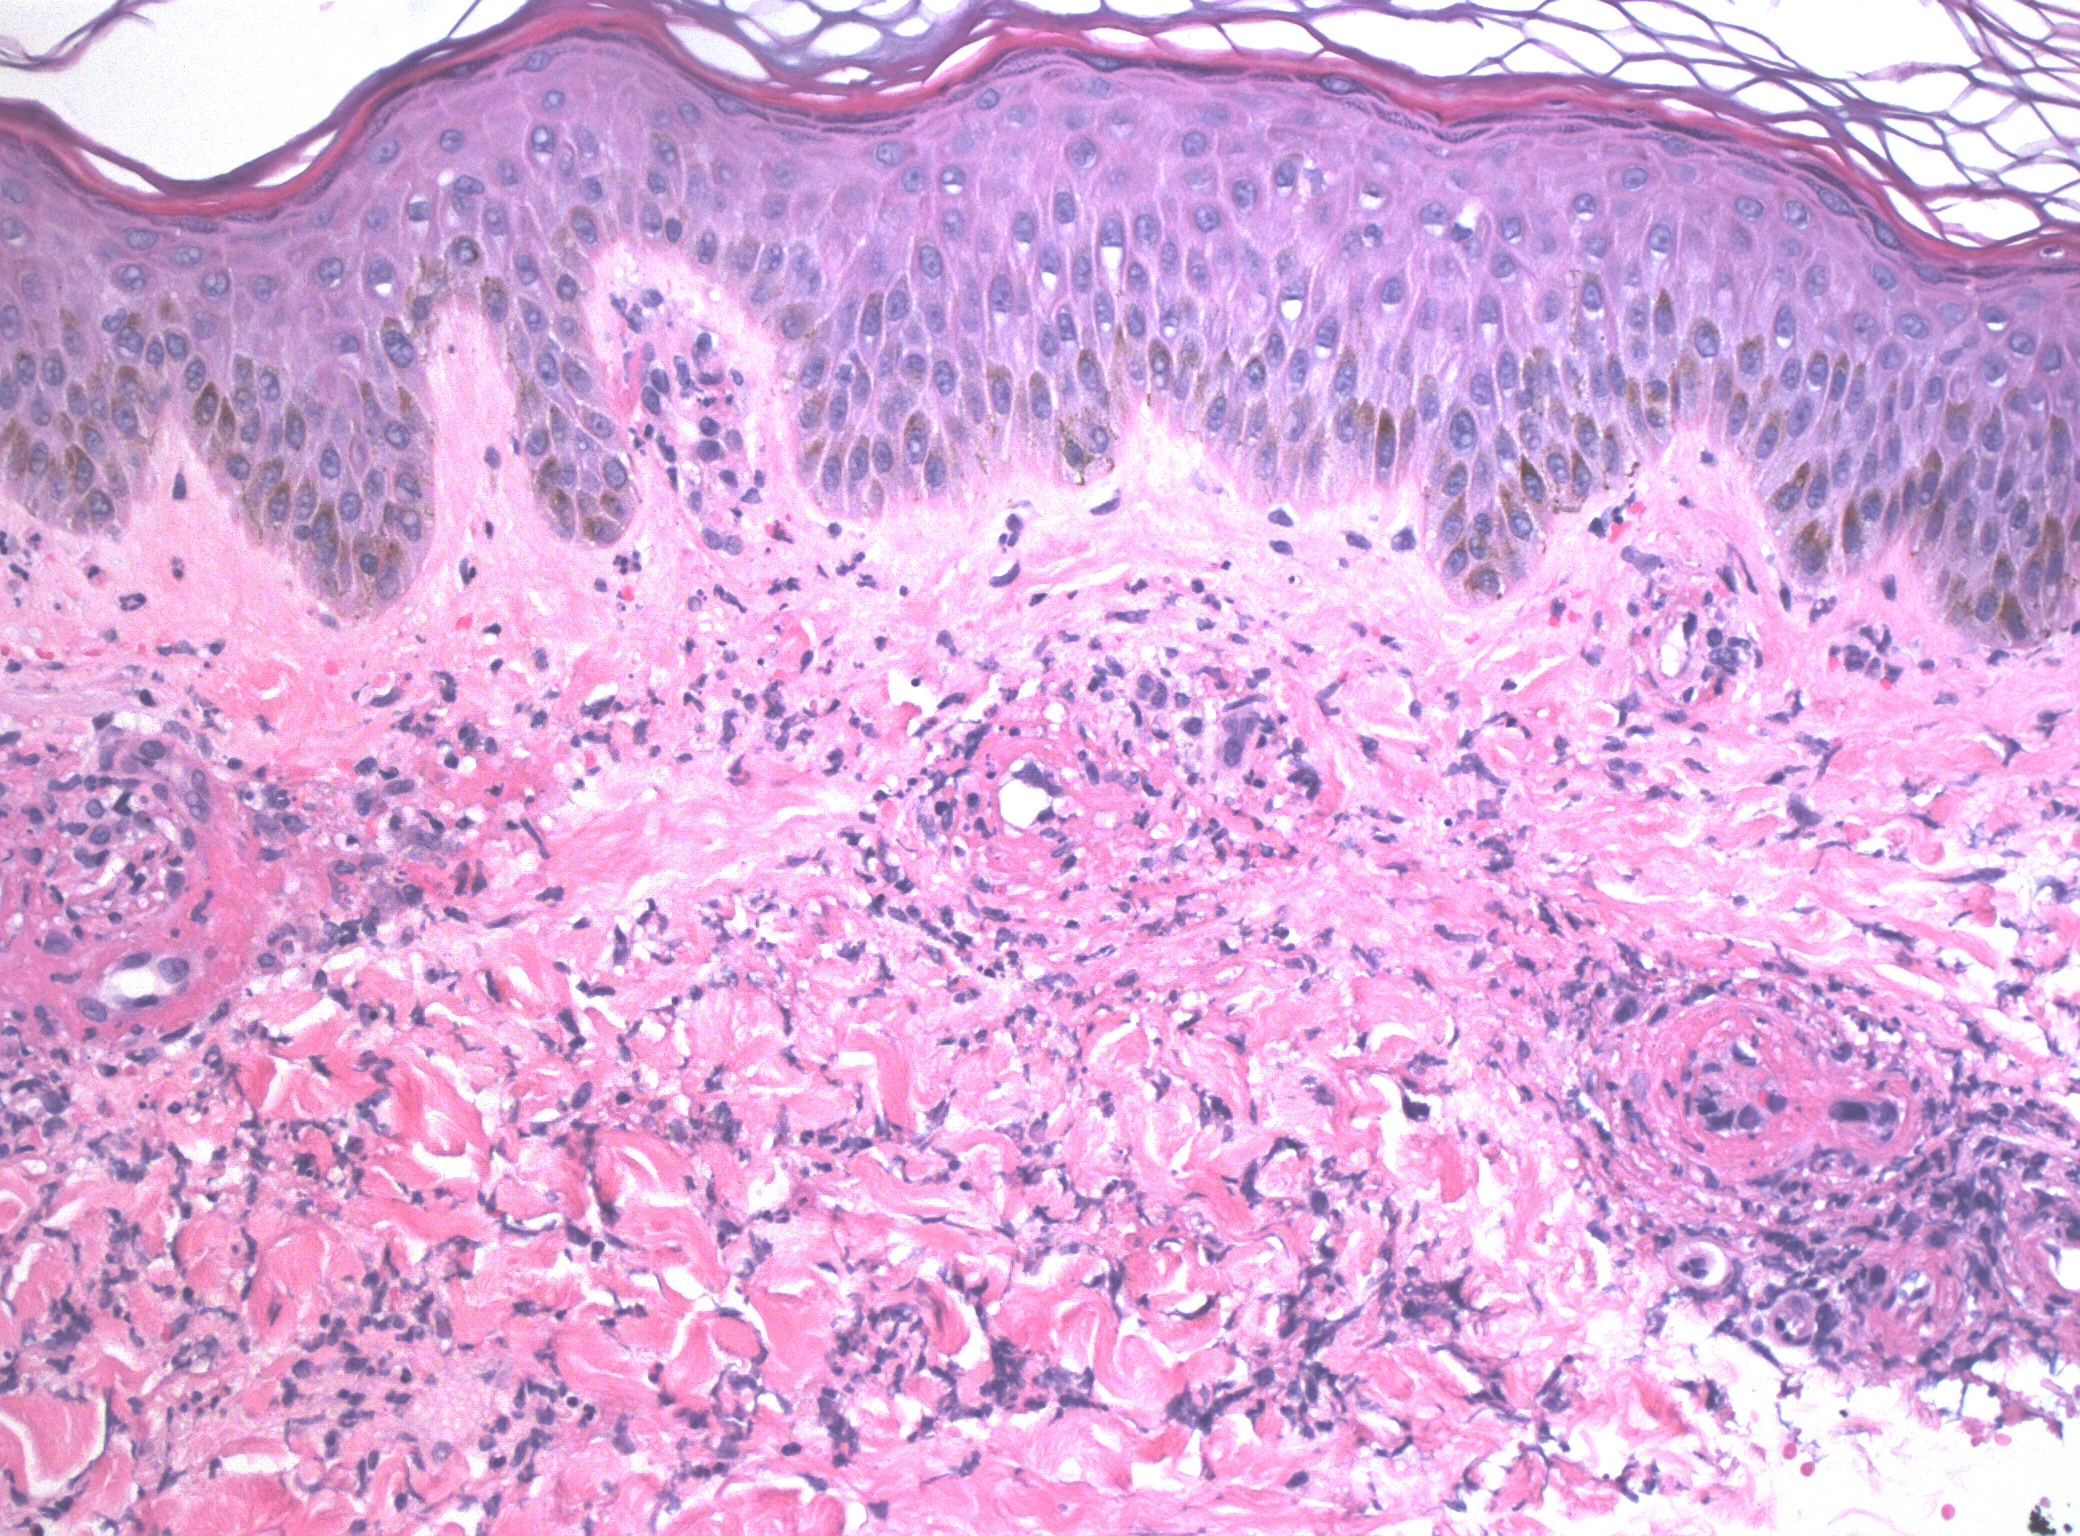

Case Presentation: A 51-year-old female with no past medical history presented with a rash that developed a week ago which started on her right calf and then progressed all over her body. She was on ibuprofen for right knee pain for the 3 weeks before her presentation. Vital signs were normal. Laboratory tests revealed leukocytosis, and elevated inflammatory markers [(erythrocyte sedimentation rate (112 mm/hr), and C-reactive protein (10.54 mg/dL)]. Antinuclear antibodies and qualitative cryoglobulin C returned positive and serum complement protein C3 was elevated (245 mg/dl). Rheumatoid factor, CCP antibodies IGG/IGC, Sjogren’s antibody (anti-SS-A/-SS-B), anti-DNA(DS), serum complement C4, ANCA profile (anti-MPO antibodies, anti-PR3 antibodies, atypical P ANCA) were negative. Thyroid stimulating hormone, creatinine, liver enzymes, prothrombin time, and partial thromboplastin time were normal. Urine analysis showed no proteinuria. Human immunodeficiency virus antibody/antigen test, hepatitis B and C serologies, syphilis screening, and Lyme serology were also negative. The rash evolved from maculopapular purpuric lesions to the development of tender vesicles, bullae, and ulcerations therefore a punch biopsy of the skin was performed, which showed leukocytoclastic vasculitis. Ibuprofen was stopped and the patient was started on a prednisone taper. The eruptions cleared and bullae started healing. The patient was diagnosed with biopsy-proven leukocytoclastic vasculitis with cryoglobulinemia secondary to ibuprofen use. She was discharged on oral prednisone, and topical triamcinolone, and referred to dermatology, and rheumatology, for further evaluation. She reported improvement at her follow-up appointment in the dermatology clinic.

Discussion: This case highlights the importance of considering medication-induced leukocytoclastic vasculitis when evaluating patients who present with unexplained rash. Ibuprofen-induced leukocytoclastic vasculitis is a rare but recognized adverse reaction to ibuprofen involving the drug acting as a hapten and initiating immune complex deposition and activation of the complement cascade in postcapillary venules, resulting in fibrinoid necrosis. Drug-induced eruptions are based on inferential evidence, usually involving a history of ingesting the suspected drug and resolution of the eruption once the drug is discontinued [1]. Diagnosis is dependent on skin biopsy but also relies on a combination of clinical features and exclusion of other causes [2].